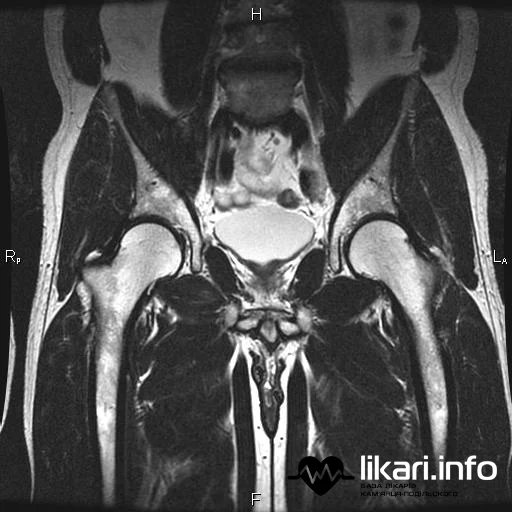

Магнітно-резонансна томографія (МРТ) кульшового суглоба — це незамінний метод раннього діагностування широкого спектру захворювань, які часто призводять до серйозного обмеження рухливості та навіть інвалідності. Цей вид дослідження набув високої популярності завдяки найвищому ступеню інформативності щодо стану м'яких тканин.

На відміну від рентгенографії чи КТ, МРТ дозволяє кваліфікованому лікарю-діагносту детально розглянути не лише кісткові структури, але й суглобовий хрящ, зв'язки, сухожилля та кістковий мозок. Це дає можливість виявити будь-які порушення тканин та проблеми на початковій стадії їх розвитку, коли лікування є найбільш ефективним.

МРТ дозволяє детально візуалізувати синовіальну капсулу, хрящі, м'язи, сухожилля, судини, а також кістки тазової області та верхню частину стегна. Обстеження призначають, якщо спостерігається:

Magnetic Resonance Imaging (MRI) of the hip joint is an indispensable method for the early diagnosis of a wide range of conditions that often lead to severe mobility limitations and even disability. This type of examination has gained high popularity due to its superior degree of informativeness regarding the status of soft tissues.

Unlike X-ray or CT, MRI allows a qualified diagnostic physician to thoroughly examine not only bony structures but also the articular cartilage, ligaments, tendons, and bone marrow. This makes it possible to detect any tissue abnormalities and problems at their initial stage of development, when treatment is most effective.

MRI allows for detailed visualization of the synovial capsule, cartilage, muscles, tendons, blood vessels, as well as the pelvic bones and the upper part of the femur. The examination is prescribed if the following are observed: